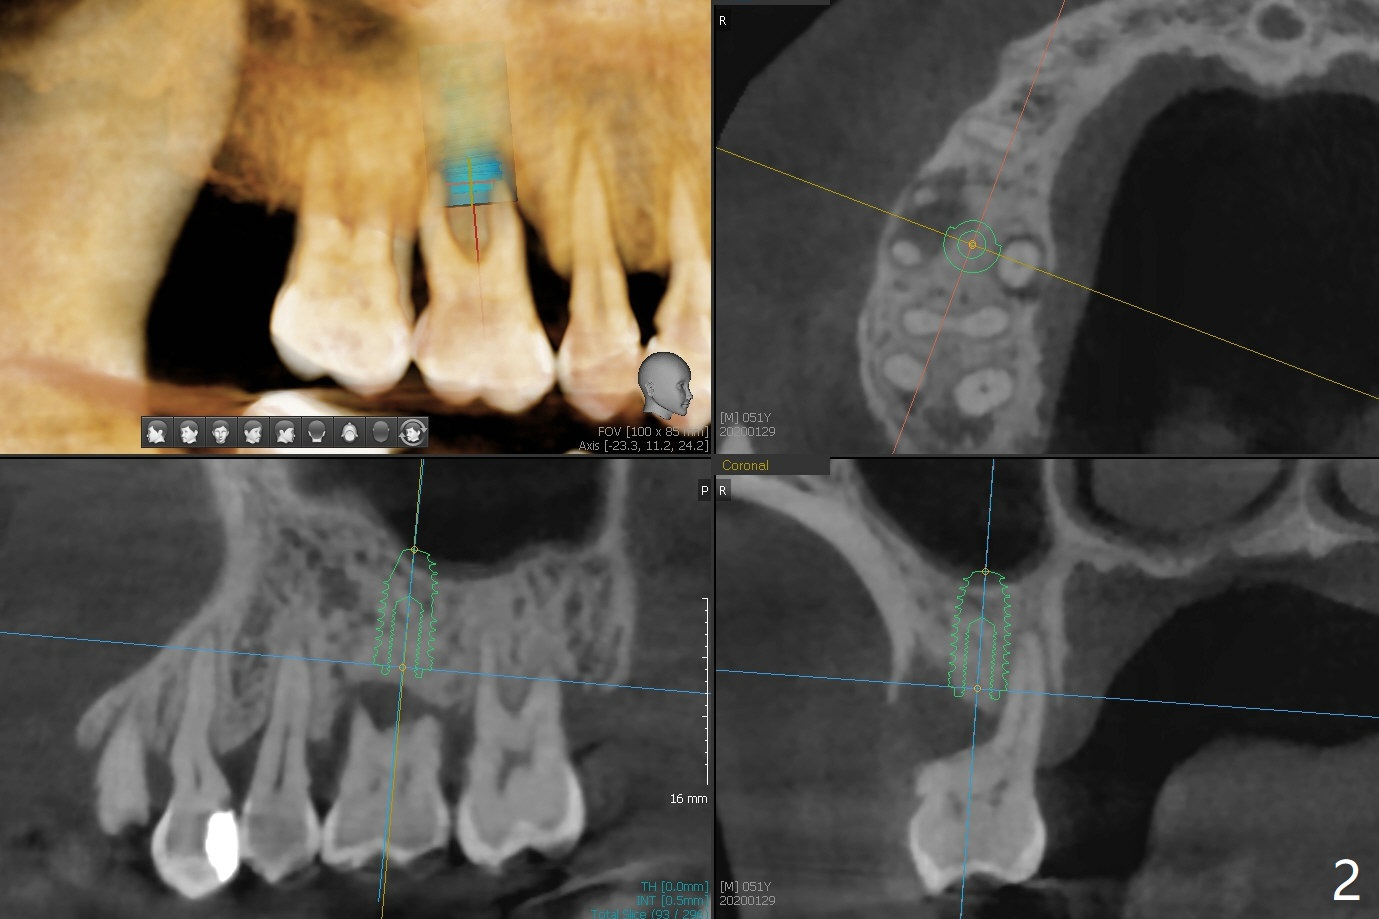

One month post cementation of the crown of #30, the opposing tooth (#3 in Fig.1) becomes symptomatic as related to the buccal furca (*). After periodontal maintenance, Arestin is placed at the furca. If the treatment does not achieve pain relief, the tooth will be removed with immediate implant free hand. Following 1.6 mm drill in the septum (Fig.2), insert its own parallel pin for PA (trajectory). After use of Marking Drill, use 4.3 mm Magic Drill with 9 mm stopper, followed by sticky bone and 4.5x10 IS dummy implant (crest level) for sinus lift (2nd PA). With confirmation of lift, insert the 1st piece of PRF membrane (small), more sticky bone and dummy. The definitive fixture will be 5x10 or 11 mm. Pack more sticky bone around the implant, especially buccal. Insert collagen dressing in the apical portion of the palatal socket if necessary. A temporary abutment (non-hex) should be easily placed. Insert 2nd piece of PRF membrane around the immediate provisional for complete seal. If it is still insecure, place periodontal dressing. In fact, the tooth is mobile with more severe bone loss 6 months later (Fig.3). Impression is taken for guide. 53 years old Male